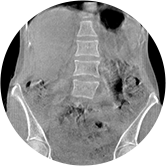

• 颈椎

• 腰椎

三维脊柱应用

精准诊断

手术方案规划

术后随访

• 脊柱评估

传统方法都是在二维平面,依靠棘突或椎弓根相对于椎体的偏移来评估脊柱侧凸。WR-3D可以更精准评估脊柱侧凸,制定手术方案,可以更直观地显示和量化椎体的平移和轴向旋转,术后评估更准确客观。

• 全身姿态评估

WR-3D能提供一种负重位状态下全身的姿态和三维空间任一平面平衡评估,使全脊柱术后评价更客观、真实 。通过各种临床参数包括骨盆、脊柱参数评价骨盆、脊柱平衡,避免由于髋膝屈曲造成的代偿性脊柱失衡的发生,WR-3D提供了三维空间任一平面平衡评估测量方法,可以更加定量地评估手术效果 。